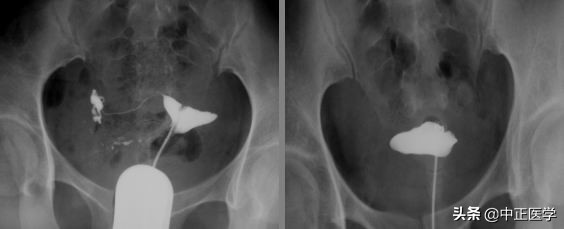

3.1、医生会选择在患者取膀胱截石位,常规消毒外阴和阴道,铺无菌巾,检查子宫的大小及位置。

3.2、以阴道窥器扩张阴道,充分暴露宫颈,再次消毒宫颈及阴道穹隆。

3.3、若应用金属导管,将造影剂充满导管,排尽空气,而后将导管插入子宫颈,堵紧宫颈外口,不至使造影剂外溢,在x线透视下观察造影剂流经宫腔及输卵管情况并摄片。